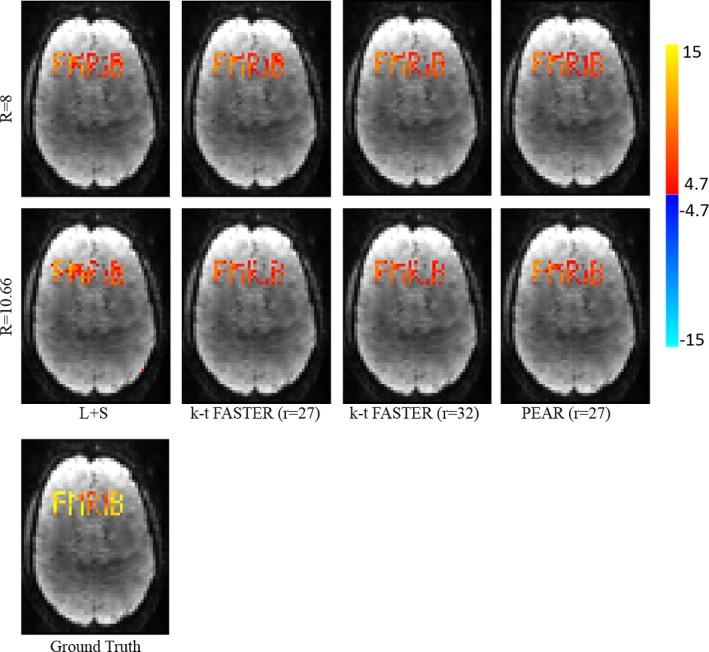

The proposed approach decomposes the fMRI signal into a component which has a fixed rank and a component consisting of a sum of periodic signals which is sparse in the temporal Fourier domain. Data reconstruction is performed by solving a constrained problem that enforces a fixed, moderate rank on one of the components, and a limited number of temporal frequencies on the other. Our approach is coined PEAR - PEriodic And fixed Rank separation for fast fMRI.

Experimental results include purely synthetic simulation, a simulation with real timecourses and retrospective undersampling of a real fMRI dataset. Evaluation was performed both quantitatively and visually versus ground truth, comparing PEAR to two additional recent methods for fMRI reconstruction from undersampled measurements. Results demonstrate PEAR's improvement in estimating the timecourses and activation maps versus the methods compared against at acceleration ratios of R = 8,10.66 (for simulated data) and R = 6.66,10 (for real data).

This paper presents PEAR, an undersampled fMRI reconstruction approach based on decomposing the fMRI signal to periodic and fixed rank components. PEAR results in reconstruction with higher fidelity than when using a fixed-rank based model or a conventional Low-rank + Sparse algorithm. We have shown that splitting the functional information between the components leads to better modeling of fMRI, over state-of-the-art methods.

结果

实验结果包括纯粹的合成模拟、具有真实时间序列的模拟以及对真实 fMRI 数据集的回顾性欠采样。通过与真实数据进行比较,对基于地面真值的定量和视觉评估,将 PEAR 与另外两种用于从欠采样测量中重建 fMRI 的最新方法进行了比较。结果表明,PEAR 在估计时间序列和激活图方面的性能优于所比较的方法,在加速比为 R=8、10.66(模拟数据)和 R=6.66、10(真实数据)时。

结论

本文提出了 PEAR,这是一种基于将 fMRI 信号分解为周期性和固定秩分量的欠采样 fMRI 重建方法。PEAR 的重建结果比使用基于固定秩的模型或传统的低秩+稀疏算法具有更高的保真度。我们已经表明,通过将功能信息分配到各个分量中,可以对 fMRI 进行更好的建模,优于现有的方法。